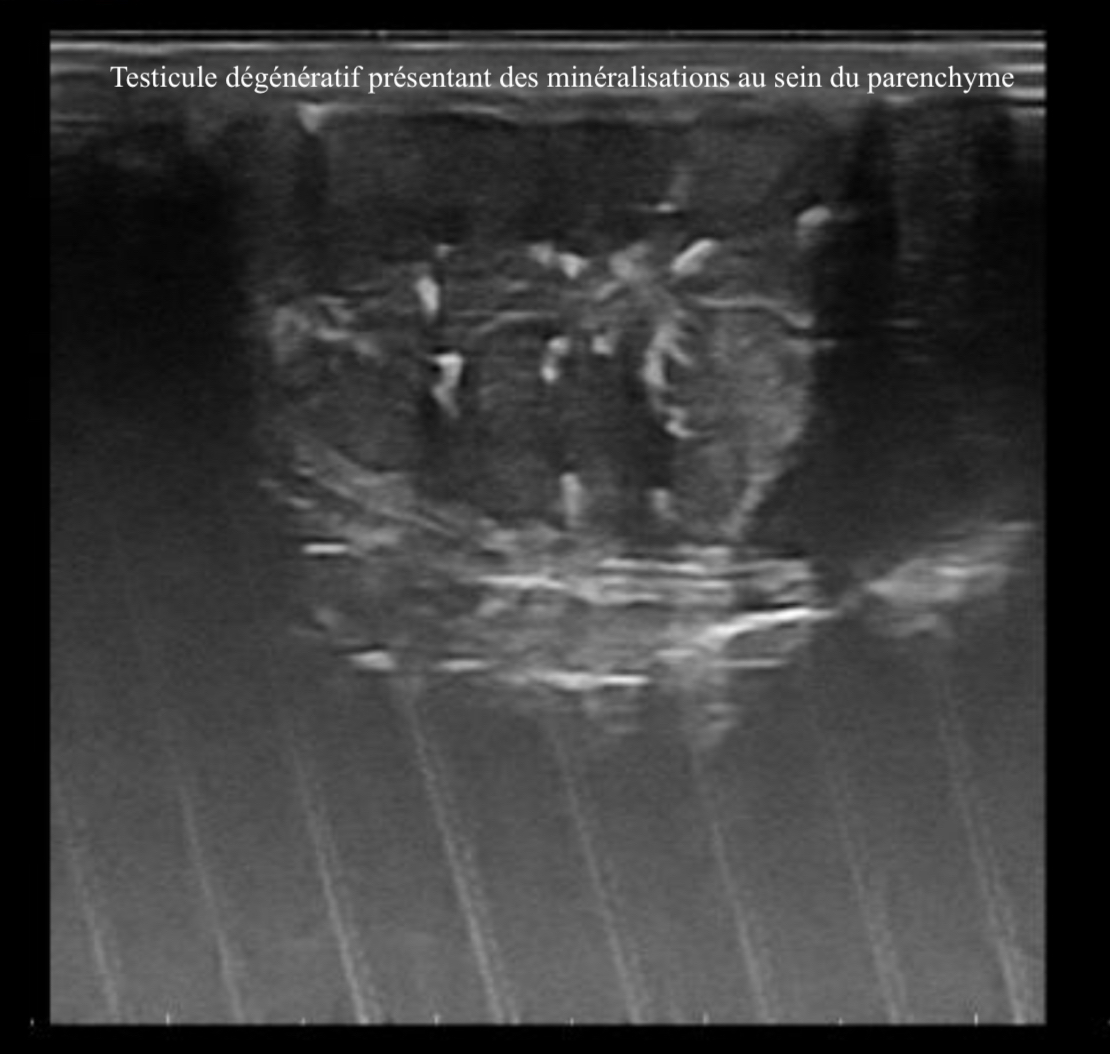

Lors de saillies infructueuses répétées chez un étalon ou de mauvaise tolérance à la réfrigération ou à la congélation de sa semence, un bilan d'infertilité peut être indiqués. Nous pouvons alors être amené à vous proposer de réaliser un spermogramme, un bilan hormonal, une échographie de l'appareil génital ou des recherches infectieuses afin d'établir un diagnostic et vous pouvoir vous proposer des options thérapeutiques pour espérer retrouver/conserver le potentiel reproducteur de votre étalon.